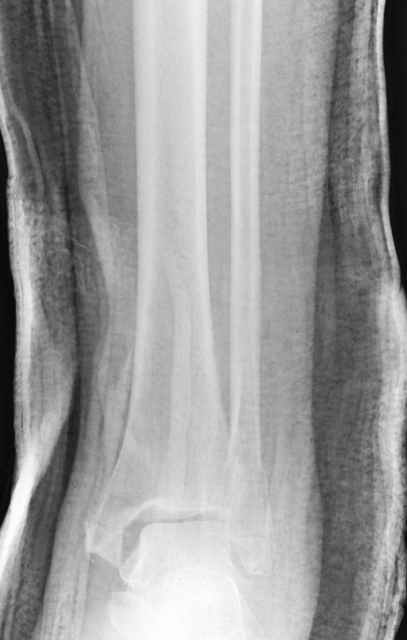

Dear all,40 y.o. man had sustained this terrible fracture falling from a motorbike.

Closed fracture.

This is really Pilon Fx (C3.3; the high energy and the extent of distal tibia comminution are defining it).

I would put simple unilateral, medially positioned external fixator (two pins in calcaneus - not to violate talus needed for later fusion, two in tibia), allow soft tissues to recover and in 2-3 weeks I would do delayed ankle fusion.

It is impossible to reconstruct the articular surface and even if somebody could do it, the cartilage will not be there/will not survive.